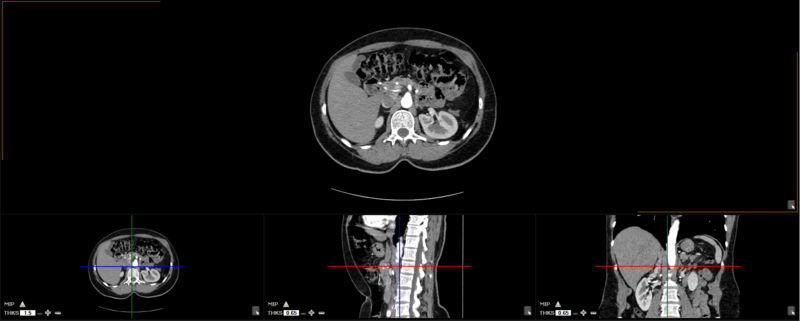

The user can choose from any of these predefined viewing protocols within the MPR mode:

Here are the different viewing protocols you can choose from: